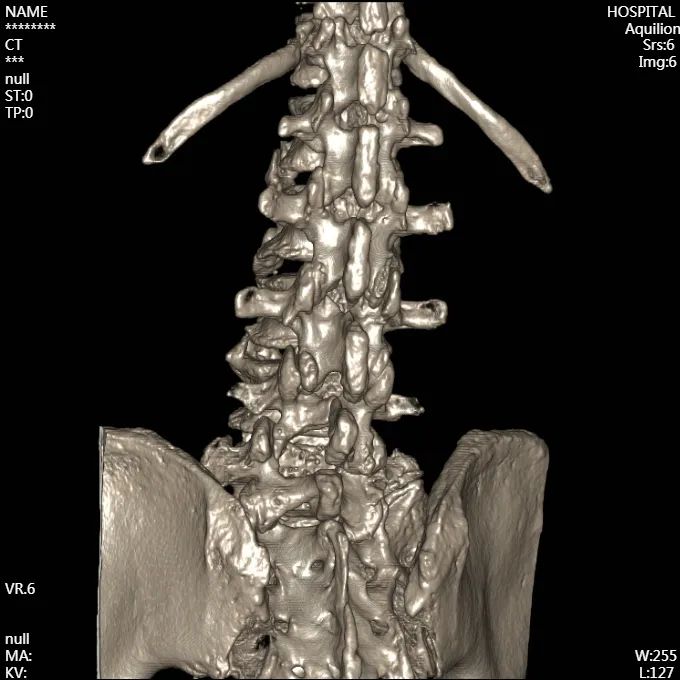

術(shù)前

X線片

腰椎CT成像